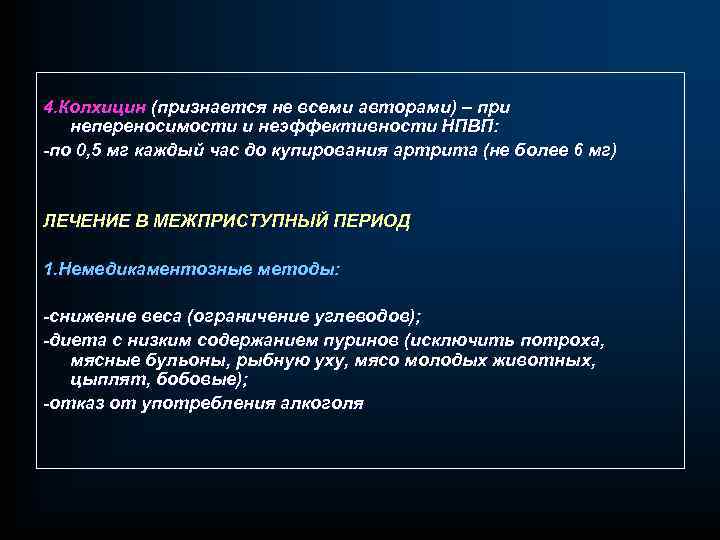

4. Колхицин (признается не всеми авторами) – при непереносимости и неэффективности НПВП: -по 0, 5 мг каждый час до купирования артрита (не более 6 мг) ЛЕЧЕНИЕ В МЕЖПРИСТУПНЫЙ ПЕРИОД 1. Немедикаментозные методы: -снижение веса (ограничение углеводов); -диета с низким содержанием пуринов (исключить потроха, мясные бульоны, рыбную уху, мясо молодых животных, цыплят, бобовые); -отказ от употребления алкоголя

4. Колхицин (признается не всеми авторами) – при непереносимости и неэффективности НПВП: -по 0, 5 мг каждый час до купирования артрита (не более 6 мг) ЛЕЧЕНИЕ В МЕЖПРИСТУПНЫЙ ПЕРИОД 1. Немедикаментозные методы: -снижение веса (ограничение углеводов); -диета с низким содержанием пуринов (исключить потроха, мясные бульоны, рыбную уху, мясо молодых животных, цыплят, бобовые); -отказ от употребления алкоголя